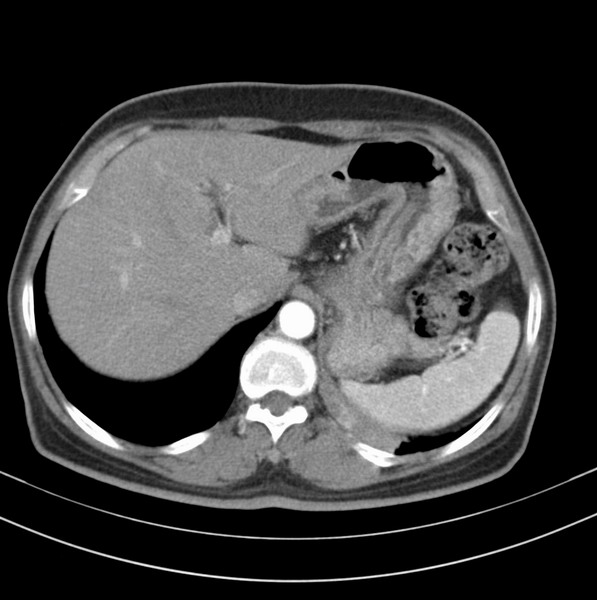

女、63

咳嗽、胸痛四个月

包绕左下肺基底段的不规则的软组织肿块,段支气管腔变形、狭窄及阻塞性炎症,病变区不规则强化,又是老年女性支持楼上看法。

考虑左肺下叶中央型肺癌伴阻塞性肺炎、支气管黏液嵌塞。

典型病例:左下肺基底段中央型肺癌,相应支气管狭窄并阻塞性炎症